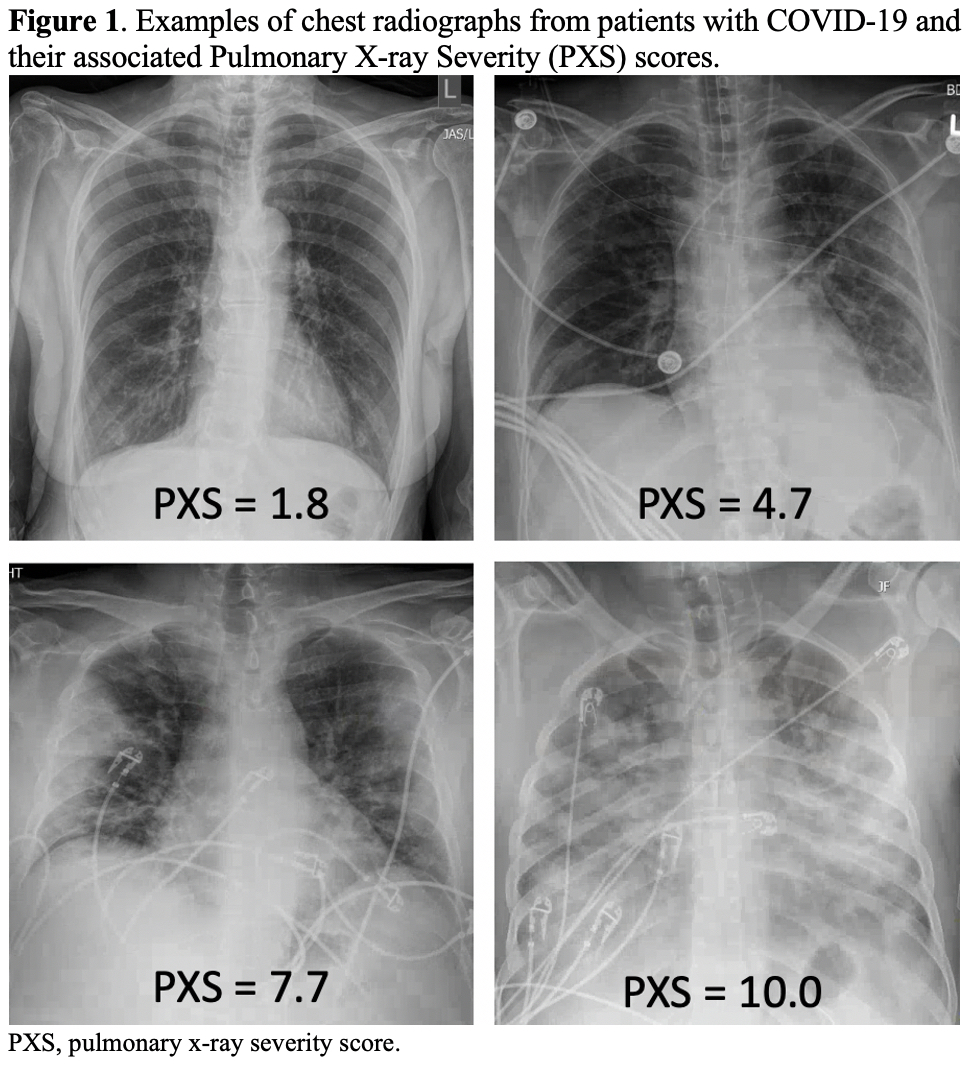

A presentation of a predicted severity scores for COVID19 chest Xray Chest X Ray Score Covid They are usually multifocal, bilateral and peripheral, but in the. This rapid advice guide examines the evidence and makes recommendations for the use of chest imaging in acute care of adult. Chest X Ray Score Covid.